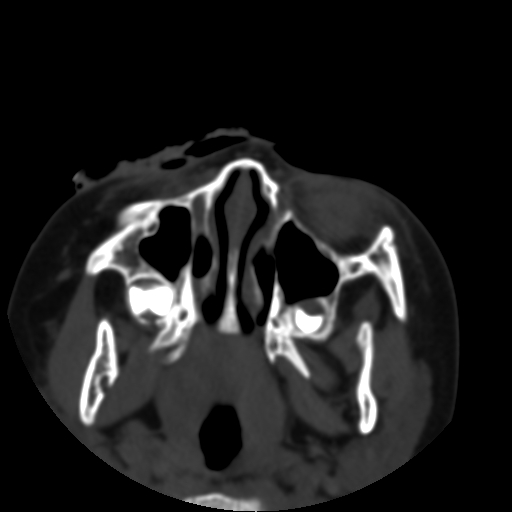

以下是引用深泽交通医院在2009-10-16 8:25:00的发言:[br]右眼环出血伴异物

以下是引用卜一在2009-10-16 15:01:00的发言:[br]右眼球挫裂伤伴异物!

以下是引用拾荒者在2009-10-17 18:38:00的发言:[br]鼻面部皮下积气,右侧睑缘及眼球壁高密度异物影,左侧眼球壁晶状体内侧缘处是圆形低密度影。低密度异物?应提请眼科医生注意。